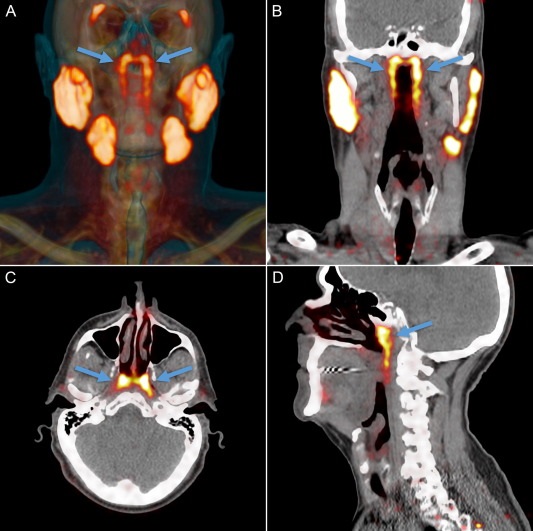

Медики обнаружили в организме человека четвертую пару крупных слюнных желез - органа, о существовании которого ранее никто не подозревал. Ученые назвали эти железы tubarial (трубными). Они находятся почти в геометрическом центре черепа, ближе к его основанию. Вероятно, из-за такого расположения железы до сих пор оставались незамеченными. Любопытно, что это первое подобное открытие за последние 300 лет пишет Radiotherapy and Oncology.

Исследователи для обнаружения и визуализации опухоли в организме взяли меченую радиоактивными изотопами глюкозу. Специалисты обнаружили, что глюкозу поглощали не только опухоли, но и некие органы, которые и оказались четвертой парой слюнных желез.

Как выяснили медики, четвертая пара слюнных желез отвечает за смазку и защиту носоглотки и зева.